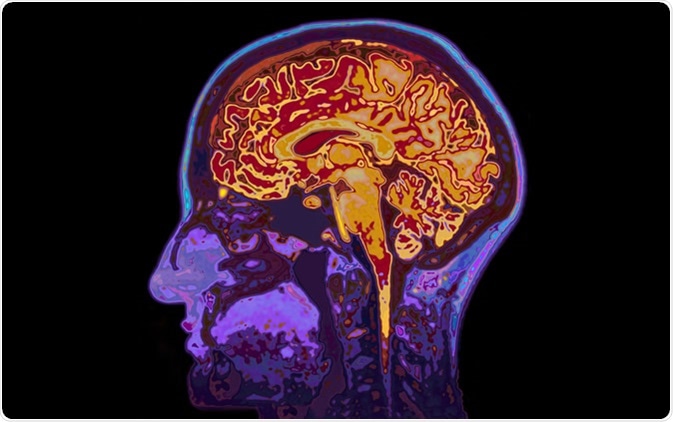

Diagnoses of the different types of dementia are usually carried out by using an array of structural and functional neuroimaging techniques (e.g., MRI, PET/SPECT, and CT scans) in addition to cognitive tests (e.g., MMSE), motor tests as well as blood/urine biochemical tests to rule out other conditions, infections, and diseases.

MRI Image Of Head Showing Brain. Image Credit: SpeedKingz / Shutterstock